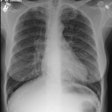

OBJECTIVE. We reviewed the imaging findings in nine patients with idiopathic giant bullous emphysema. This progressive condition is characterized by large bullae, usually seen in association with several forms of emphysema, and usually occurs in young men, most of whom are smokers. MATERIALS AND METHODS. Nine patients with chest radiographic evidence of a bulla or bullae occupying at least one third of a hemithorax, who had also been examined with high-resolution CT, were included in this retrospective study. We examined the size, distribution, and locations of bullae. On high-resolution CT scans, bullae were categorized as predominantly subpleural or intraparenchymal. RESULTS. In eight of the nine cases, the chest radiographs showed variable asymmetry in the distribution of bullae. Bullous disease involved predominantly the upper lobes. High-resolution CT showed bullae from 1 to 20 cm in diameter, but most were 2-8 cm in diameter. Paraseptal emphysema and subpleural bullae were the predominant findings in all nine patients. Seven patients had separate centrilobular emphysema of various degrees and intraparenchymal bullae. None of the intraparenchymal bullae were larger than 2-3 cm. Additionally, two non-small-cell lung cancers were seen in our series. CONCLUSION. The dominant and consistent feature seen on high-resolution CT scans in both smokers and nonsmokers is extensive paraseptal emphysema merging into giant bullae. Associated centrilobular emphysema, seen in cigarette smokers, is the important variable finding for determining the extent of underlying parenchymal disease, which may help in the preoperative assessment of giant bullous lung disease.